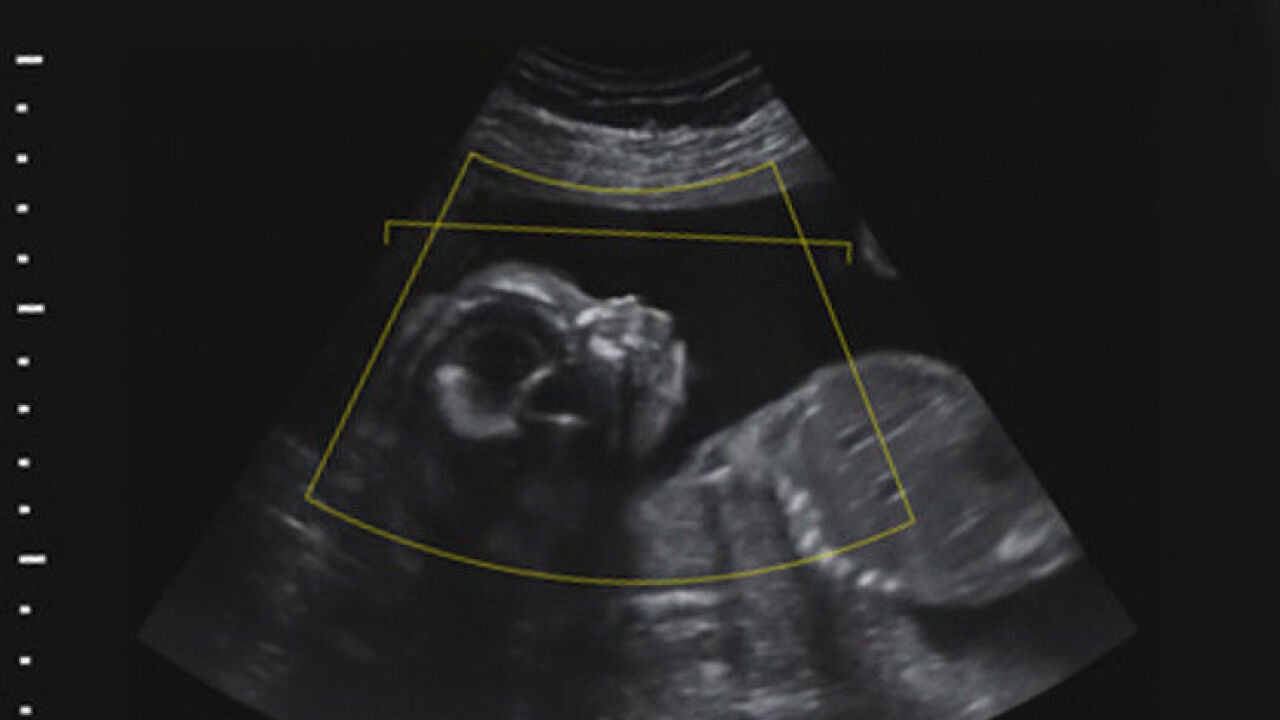

Una pareja de Los Ángeles ha presentado una denuncia contra una clínica especializada en fecundación in vitro. Se dieron cuenta de que se habían intercambiado dos óvulos fecundados y habían tenido la hija de otra pareja.